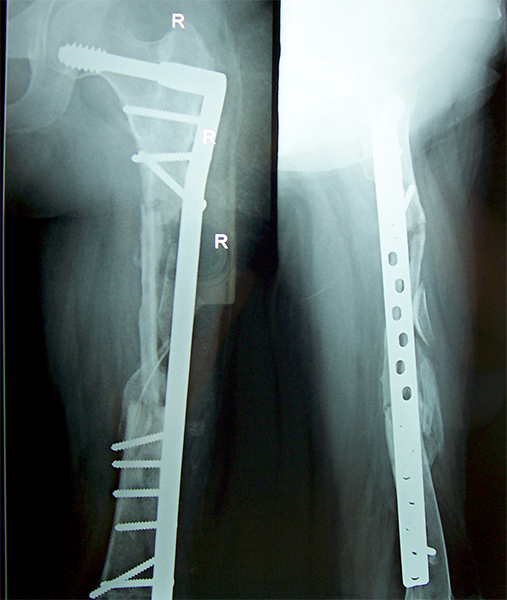

Case:5 Ewing sarcoma with implant failure

Refixation with Angle Bladed Plate and Sever Graft

Ewing's Post Nailing and Bone Grafting

3 Months Post -Op

6 Months Post-Op